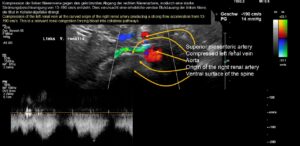

- eine hochgradige Kompression der linken Nierenvene

Der klinisch vermutete und intraoperativ bestätigte Tronc réno-rachidièn konnte zunächst sonographisch nicht visualisiert werden, da aufgrund des hohen Staudrucks im Spinalkanal kein effektiver Blutfluss vorhanden war, der ein Doppler-Signal erzeugt hätte. Dies war Ausdruck des enormen intraspinalen Drucks, der dem Druck in der komprimierten linken Nierenvene entsprach.

Darüber hinaus wurde der Stauungsdruck im Spinalkanal durch große Blutmengen über die aufsteigende Lendenvene links erhöht, was zu neurologischen Ausfällen in Form einer extrem schmerzhaften Spastik im linken Bein führte.